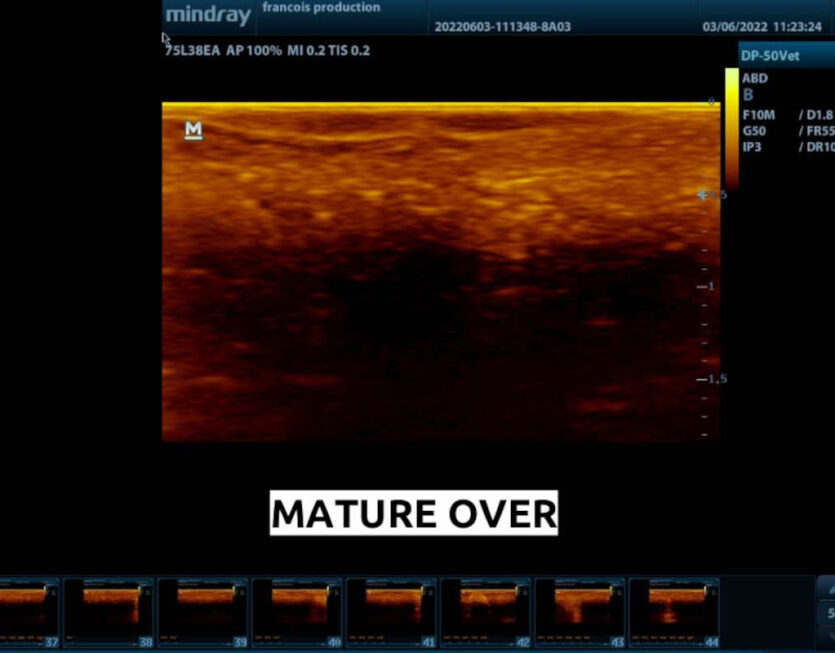

AQUASCAN® is a field software application for ultrasound devices. It embeds AI models in an IoT device to automatically assist operators. AQUASCAN ® ensures standardized and reproducible results, enhancing productivity and skilled staff availability, and complementing human expertise by enabling greater clinical focus.

- AI-based classification: deep learning models with option for custom development, continuously improved through retraining on enriched data.